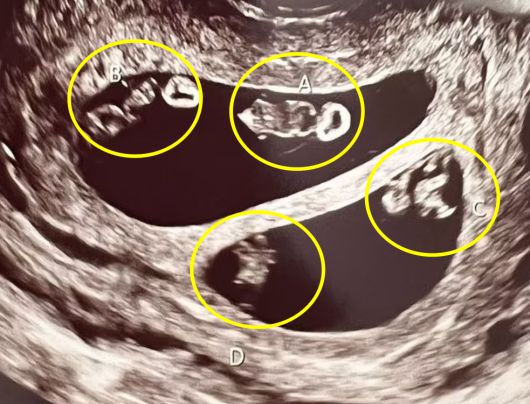

7000만 분의 1 확률로 두 쌍의 일란성 쌍둥이를 동시 임신한 여성(왼쪽)의 초음파 영상 캡쳐(오른쪽) |

임신이라는 사실을 직감한 뒤 병원을 찾았을 때, 초음파 검사를 하던 담당 의사는 의아함에 고개를 갸우뚱거렸다. 그녀의 자궁 안에서 총 4명의 태아가 자라고 있으며, 이는 네 쌍둥이가 아닌 일란성 쌍둥이 2쌍으로 추정됐기 때문이다.

7000만 분의 1 확률로 두 쌍의 일란성 쌍둥이를 동시 임신한 여성의 초음파 영상 캡쳐 |

네스의 자궁에서 자라는 일란성 쌍둥이는 남자아이 2명, 여자아이 2명으로 확인됐다.

담당 의사는 “네 쌍둥이가 아닌 일란성 쌍둥이 두 쌍을 동시에 임신하는 경우는 처음 봤다. 당초 초음파 검사를 통해 이를 확인했을 때, 이런 ‘현상’이 가능한 지 알수가 없어서 곧바로 관련 자료를 찾아봐야했다”고 전했다.